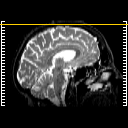

overlay : Slice 51

Slice 51

MRCBFCBF with

T1PDT2T1PDT2